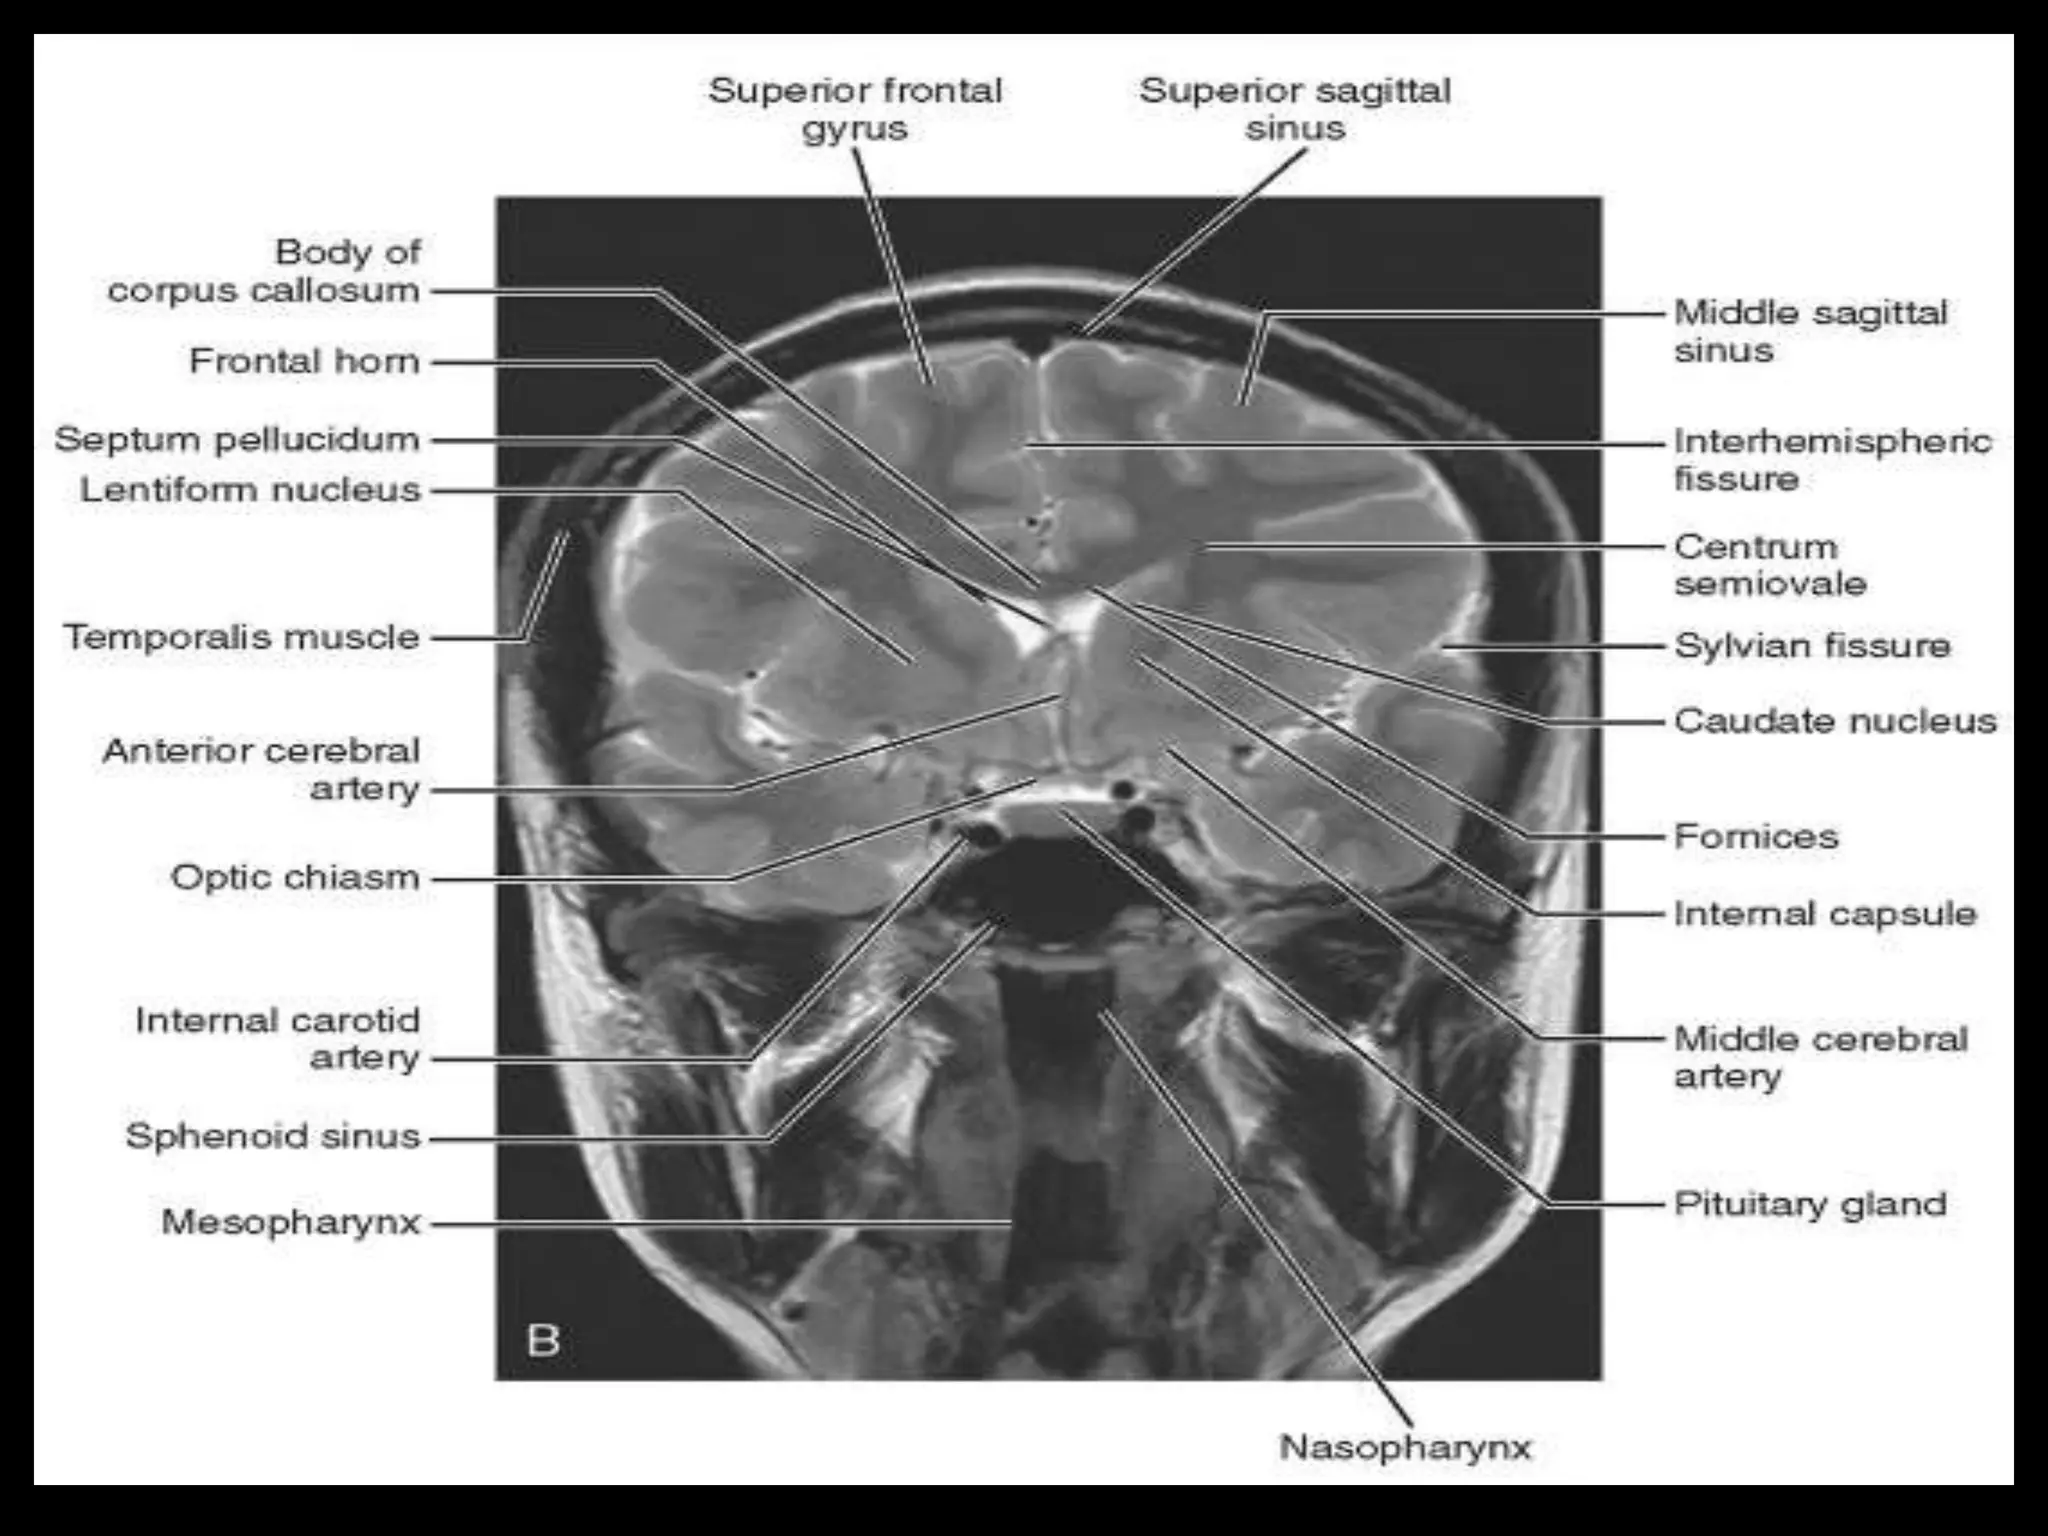

Sectional Anatomy:

Normal Axial CT and MRI Anatomy.

On CT and MR scans, the brain has been briefly viewed in

infratentorial and supratentorial sections, as described below.

CT scans are performed with a 15- to 20-degree angulation to

the canthomeatal line at 8-mm increments. MRI scans are

generally obtained parallel to the AC-PC line in the axial plane

with 6-mm slice thickness. Using the sagittal view, the coronal

sections are acquired parallel to the brain stem, and the

sagittal sections are obtained perpendicular to the axial

section.

Sectional Anatomy: NormalAxial CT and MRI Anatomy. On CT and MR scans, the brain has been briefly viewed in infratentorial and supratentorial sections, as described below. CT scans are performed with a 15- to 20-degree angulation to the canthomeatal line at 8-mm increments. MRI scans are generally obtained parallel to the AC-PC line in the axial plane with 6-mm slice thickness. Using the sagittal view, the coronal sections are acquired parallel to the brain stem, and the sagittal sections are obtained perpendicular to the axial section. On MRI studies, cranial nerves IX and X can be demonstrated at this level because they emerge from the postolivary sulcus. The posterior aspect of the cerebellar hemispheres is outlined by the inferior portion of the cisterna magna.